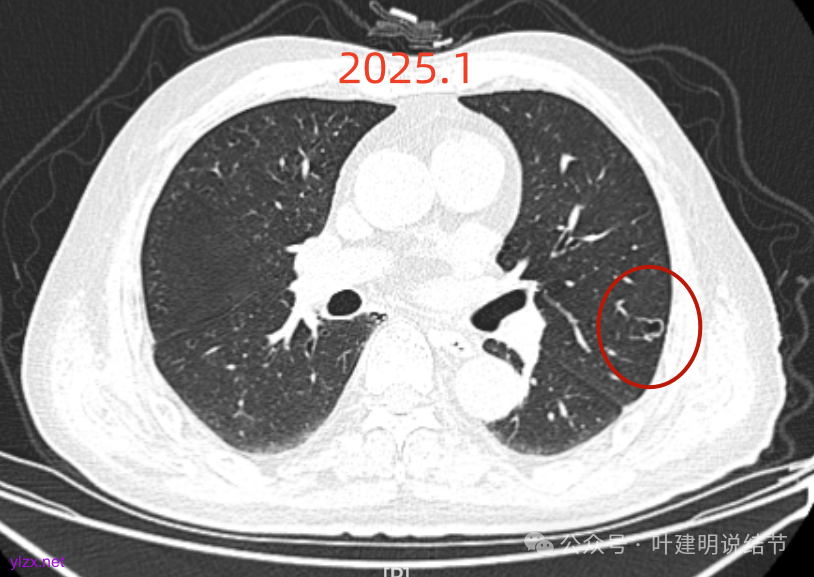

先来看2025年1月的影像:

再看2023年时的影像主要层面:

左肺上叶红色这处是囊腔型病灶,囊壁略不均,似有微小血管进入囊壁,对比2023年4月整个囊腔来讲有扩大,需要考虑囊腔型肺癌的可能性大。右侧蓝色的并不是典型囊腔型肺癌的表现,再加上两肺绿色这些慢支肺气肿与肺大泡的影像,右侧的就更加不确切,至少近期不能够考虑右侧也要开刀的事情。其实左侧的主病灶相对于其他表现更典型的囊腔型肺癌来说,由于囊壁密度偏高,也不是百分百必定是肺癌。我的想法还是先等脑梗情况稳定,并且间隔4~6个月复查病灶再有进展在考虑单孔胸腔镜下局部切除就可以。淋巴结可以考虑采样,但一般不至于阳性。破是不会切破的。消融不建议,囊腔灶更难通过穿刺获得病理依据,况且东西在边上,能局部楔切,当然首选手术。意见供参考!

左侧这个病灶总体上看仍是囊腔型肺癌可能性大些,但因为其两肺存在多发肺大泡的基础,而且囊壁除了结节状高密度的以外,其他的部分虽欠均匀,但差别并不太大。所以100%恶性还是难以认定的。假如没有脑梗情况,位置在边上,早点切了明确并去除病灶当然是可行的。但在反复脑梗发作的情况下,本身要神经内科情况稳定再手术较为安全,加上无法确切认定必恶性,再适当的随访也不至于影响预后。所以仍是利弊权衡与如何平衡的事情。对于这种囊腔灶,或囊肿为表现的肺癌,其实穿刺不容易阳性,针越过组织的距离并不长,其内又是空的或是液体性质的。从临床经验来看,囊腔型肺癌若囊壁是实性的,确实低分化类型的更常见些,相对风险较高些。但若是囊壁磨玻璃成分的,则也仍是贴壁为主型多见。而且从大小来讲,个人总觉得囊腔部分不能算大小,肿瘤的有形成分应该是减去空腔部分的,所以不能认定CT上测量的包括囊腔部分的来算肿瘤大小的T值。